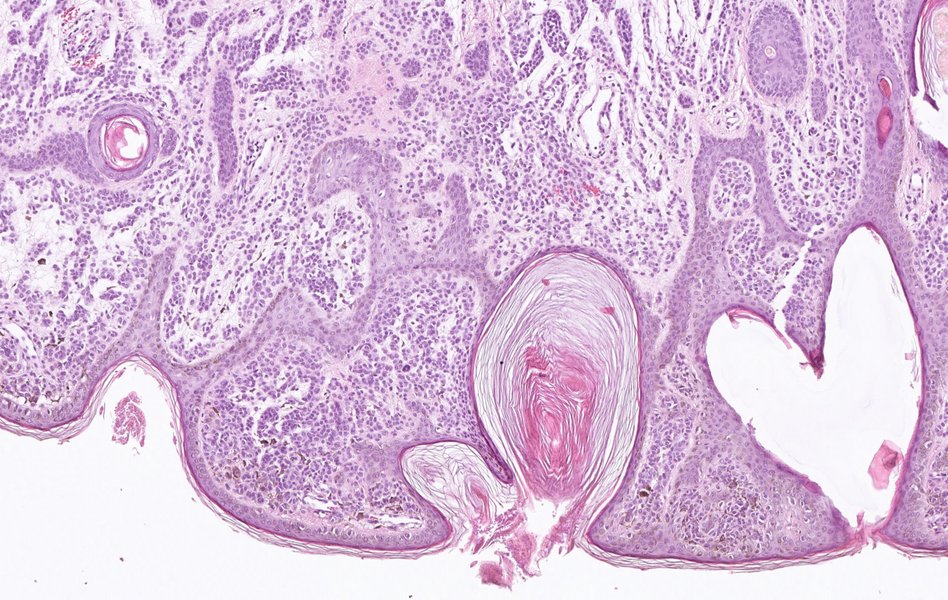

Der schwarze Hautkrebs, das sogenannte maligne Melanom, ist für den Großteil der Hautkrebs-bedingten Todesfälle verantwortlich. Nach wie vor stellt bei Verdacht auf schwarzen Hautkrebs die Untersuchung einer Gewebeprobe den Goldstandard in der Diagnostik dar. Die Proben werden so gefärbt, dass sich verschiedene Gewebestrukturen im mikroskopischen Bild unterscheiden lassen. Das ermöglicht es dem erfahrenen Pathologen zu entscheiden, ob es sich um ein Melanom handeln könnte oder nicht.

BU: Histopathologisches Präparat eines gutartigen Muttermals (Nävus)